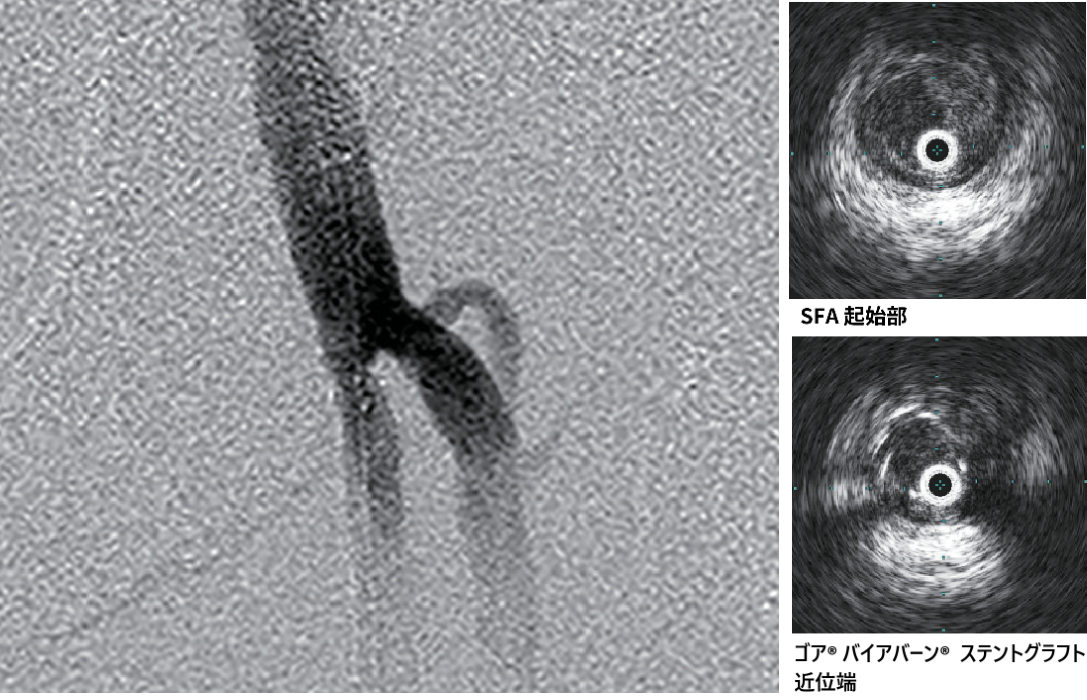

- IVUSにて遠位部のヘルシーな部分をマーキングし、バイアバーン® ステントグラフト径6.0/長250 mm を留置(図2)。

- 造影上は良好な血流改善を得られたが、IVUSではSFA起始部にプラーク残存を認めた(図3)。

- プラークをフルカバーするため、SFA起始部にバイアバーン® ステントグラフト径6.0/長50 mmを追加留置(図4)。